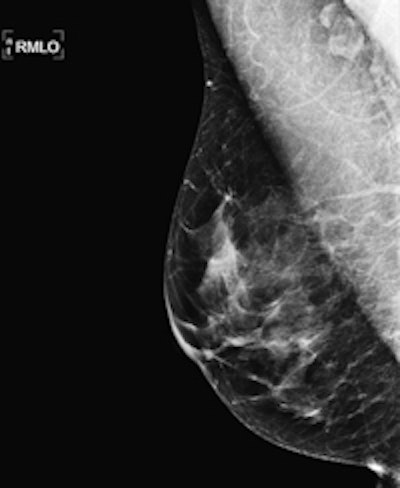

Radiologists reviewed maximum intensity projection (MIP) images first to look for significant enhancement, and then reviewed the complete abbreviated protocol consisting of MIP and first postcontrast subtracted fast images (and optionally nonsubtracted source images) to determine a diagnosis. Only after that was the regular full diagnostic protocol analyzed.

The MRI acquisition time for the full diagnostic protocol was 17 minutes, compared with three minutes for the abbreviated protocol. Average time to read the single MIP was 2.8 seconds, compared with 28 seconds to review the entire abbreviated protocol. The readers detected 11 breast cancers (four ductal carcinomas in situ and seven invasive cancers; all T1N0 intermediate or high-grade), for an additional cancer yield of 18.2 per 1,000, the researchers wrote.

MIP readings were positive in 10 (90.9%) of 11 cancers and showed a negative predictive value (NPV) of 99.8% (418 of 419). Readers using the complete abbreviated protocol diagnosed all 11 cancers. Specificity and positive predictive value (PPV) of the abbreviated protocol versus the full diagnostic protocol were equivalent (94.3% versus 93.9% and 24.4% versus 23.4%, respectively).